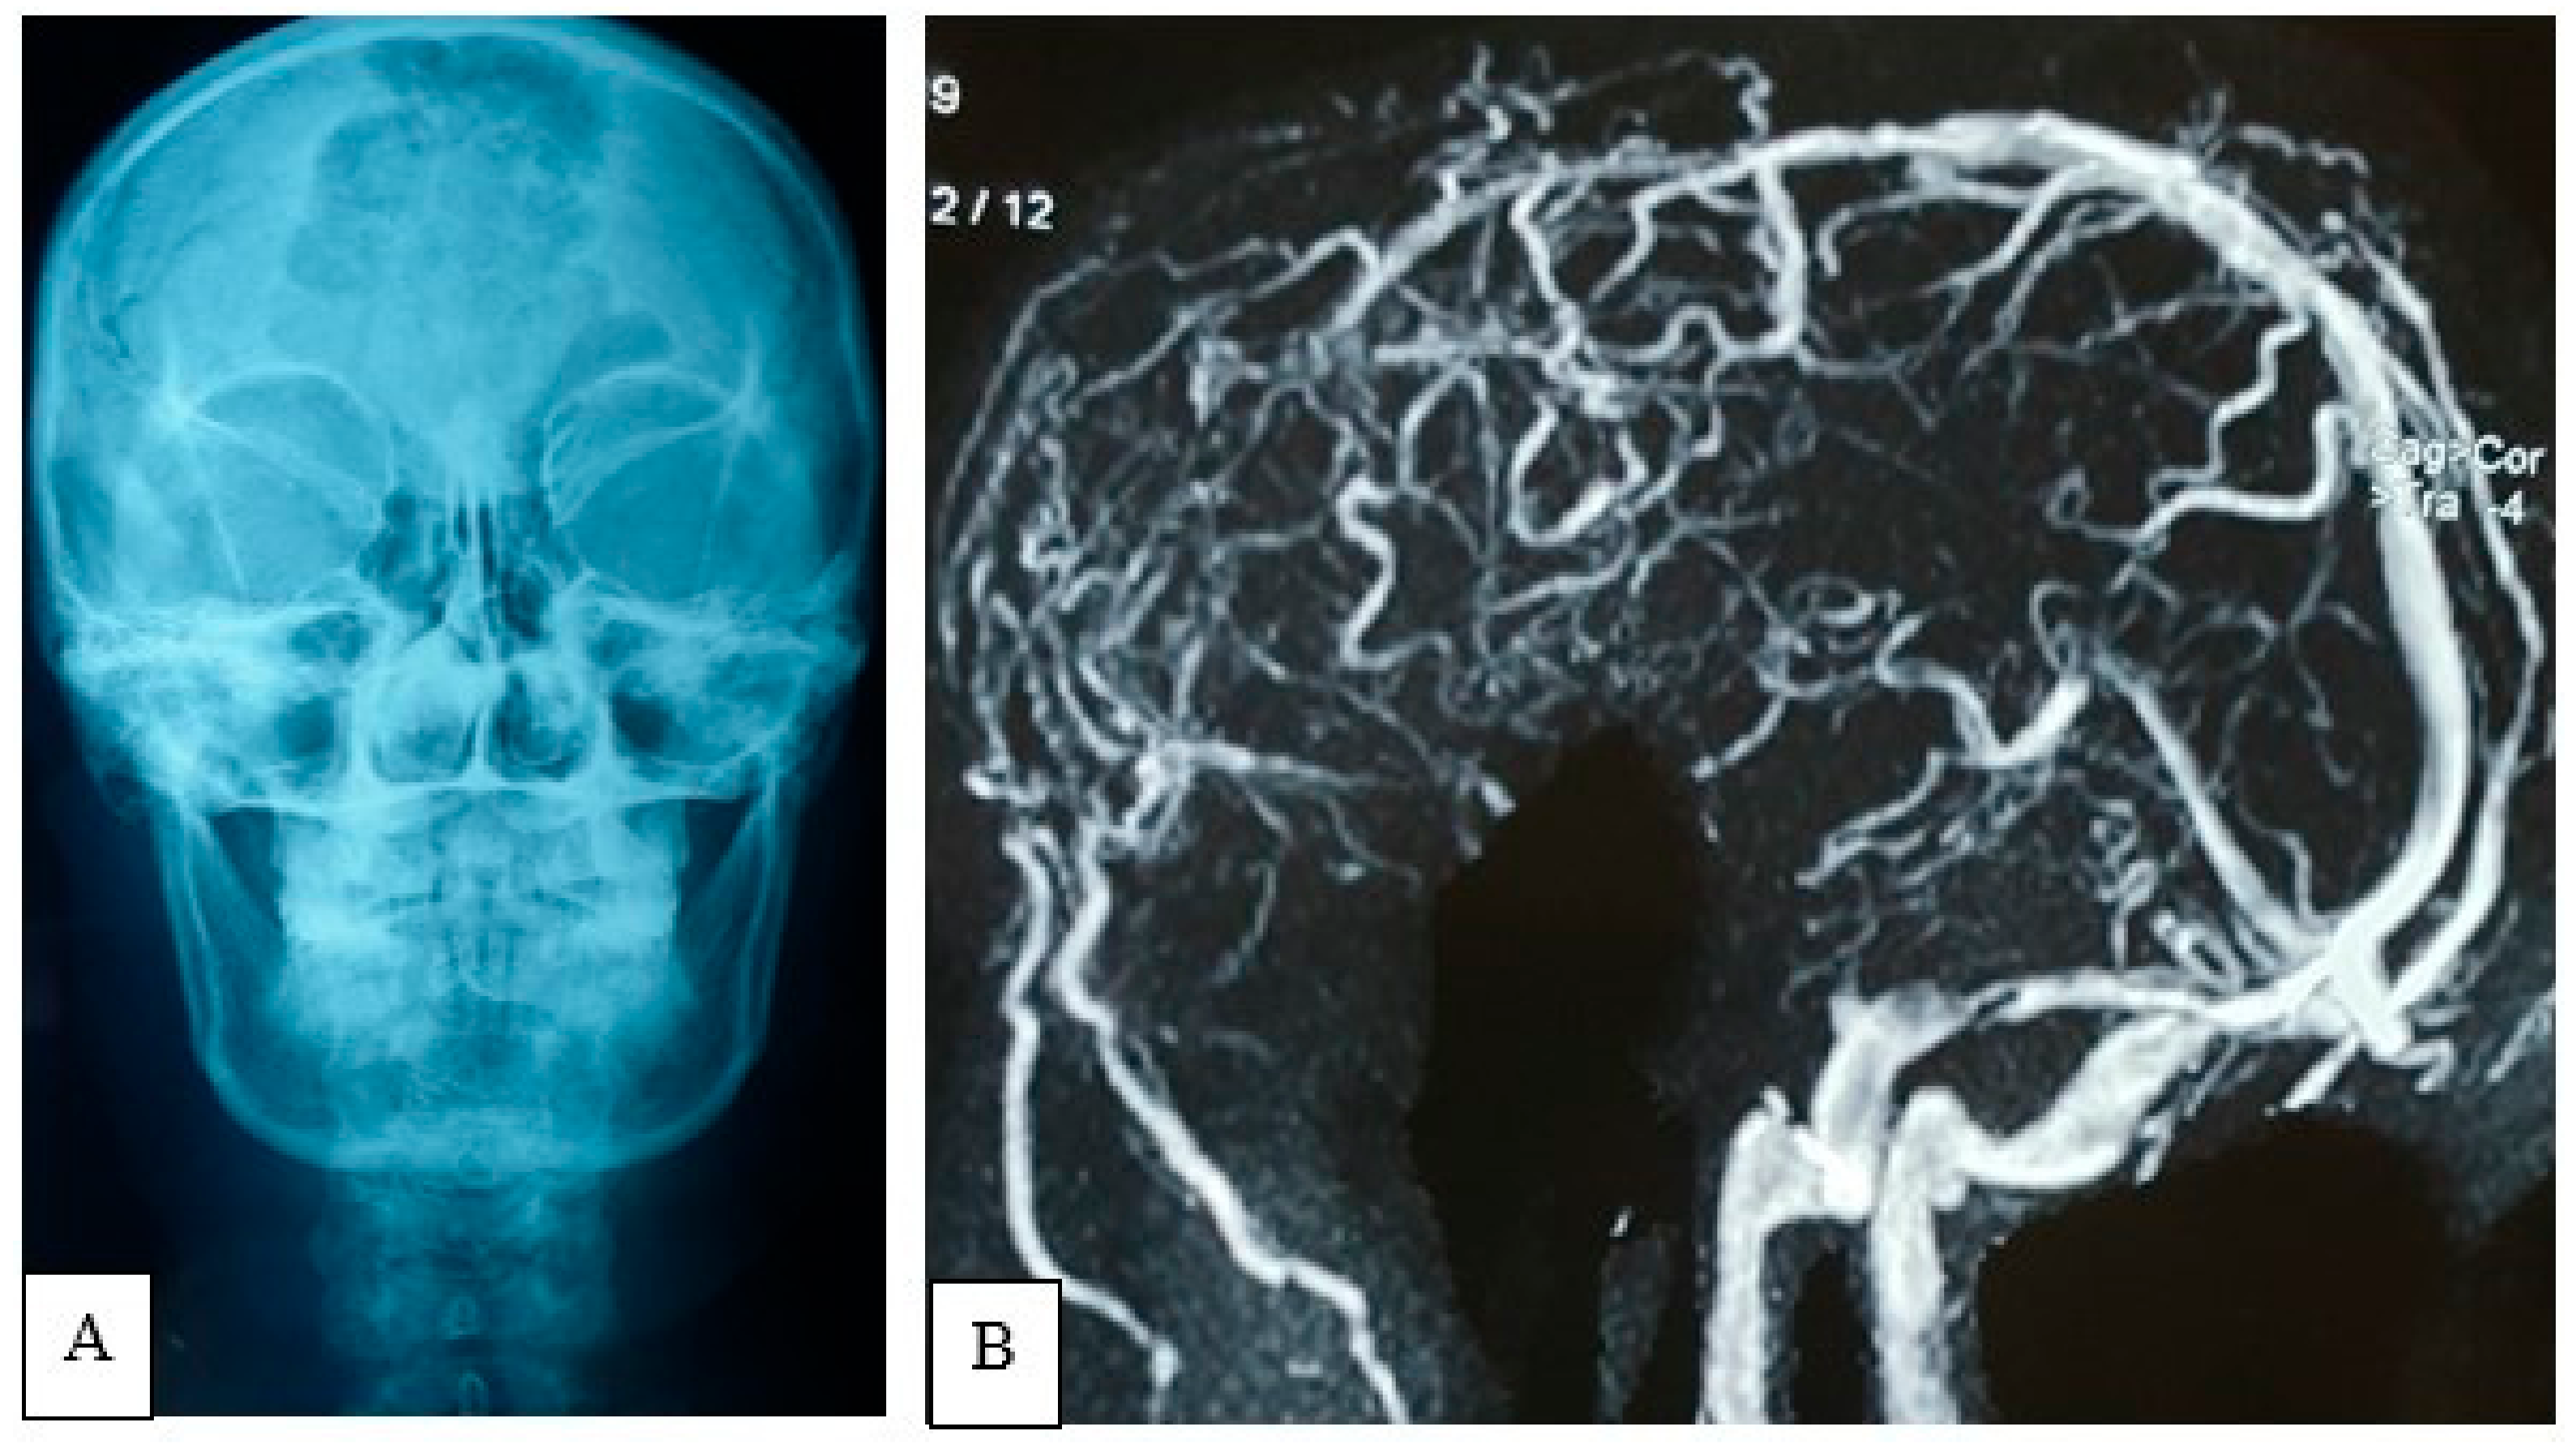

2.4.3. Preoperative Imaging

2.4.4. Surgical Procedure